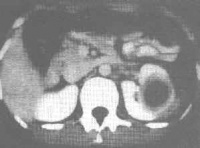

肾脓肿是指肾脏实质因炎症化脓而被破坏,形成一脓性包囊,肾功能完全丧失,常见于上尿路梗阻的患者。